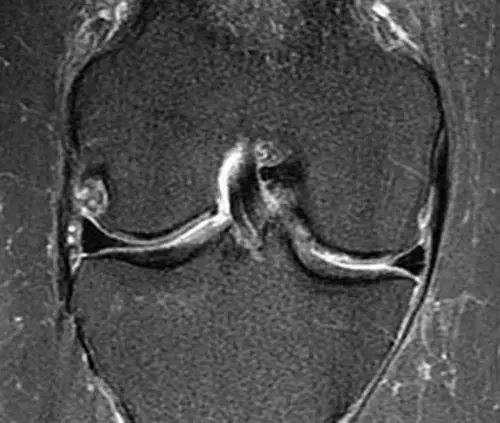

Located in Maui, Osteopathy on Maui, led by Dr. Brian Peternell D.O., is a dedicated osteopathic practice that blends traditional hands‑on manipulation with modern regenerative techniques. The clinic’s core identity centers on restoring the body’s innate healing capacity through precise, anatomy‑focused care for musculoskeletal conditions across the island. The team emphasizes a non‑surgical, evidence‑based approach, offering ultrasound‑guided PRP injections to accelerate tissue repair in tendons, ligaments, and joints. Complementary services such as osteopathic manipulation and cranial osteopathy support overall biomechanics, while targeted PRP therapy provides regenerative orthopedics for knee, hip, shoulder, hand, and ankle injuries. This philosophy prioritizes functional recovery and pain reduction without reliance on drugs or extensive surgery. Dr. Peternell brings board certification in Neuromusculoskeletal Medicine and Osteopathic Manipulative Medicine, backed by extensive training and a commitment to patient‑centered care. His expertise, combined with a supportive clinical environment, positions the practice as a trusted source for non‑surgical joint pain relief and regenerative medicine in Maui.